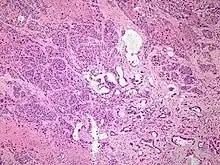

Histopathology

The most common form of pancreatic cancer (adenocarcinoma) is typically characterized by moderately to poorly differentiated glandular structures on microscopic examination. There is typically considerable desmoplasia or formation of a dense fibrous stroma or structural tissue consisting of a range of cell types (including myofibroblasts, macrophages, lymphocytes and mast cells) and deposited material (such as type I collagen and hyaluronic acid). This creates a tumor microenvironment that is short of blood vessels (hypovascular) and so of oxygen (tumor hypoxia).[2] It is thought that this prevents many chemotherapy drugs from reaching the tumor, as one factor making the cancer especially hard to treat.[2][3]